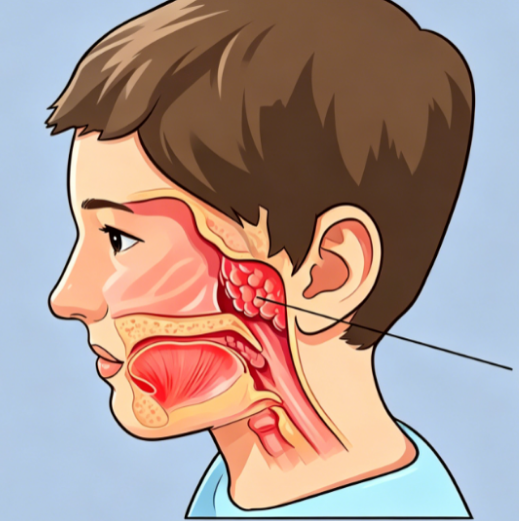

新型冠状病毒虽主要是以肺为主要靶器官,但也经常会表现多种胃肠道症状,甚至可作为首发症状,重症患者可出现消化道出血,其中以腹泻最为多见,腹泻次数、持续时间以及严重程度不同,有文献报道腹泻可作为预测重症患者的独立危险因素。也有部分患者可能只有胃肠道的症状,而缺乏呼吸系统的症状,需要引起重视。

1、病毒攻击:新冠病毒本身可能会感染胃肠道黏膜,导致病毒性肠炎,从而出现腹泻。

2、肠粘膜屏障受损,有毒物质及其它有害菌或病毒及其代谢产物更易入血,继发细菌感染,导致肺部及其它部位感染加重。

目前并没有治疗新冠的特效药,要想康复,拥有强大的免疫力是最可靠的保障,而肠道是最大的免疫器官,70%的免疫细胞位于肠道,因此,保护肠粘膜屏障,积极处理腹泻、腹胀、便秘、改善胃肠功能,也是改善免疫力的关键一环!